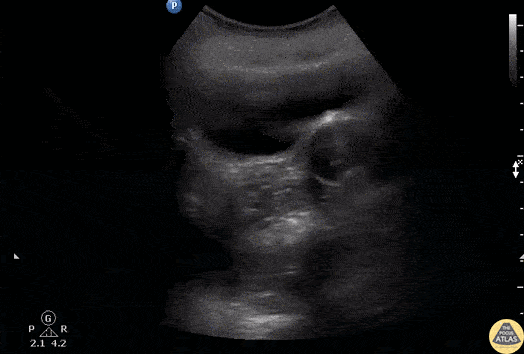

A young female presented to the ED with sudden pelvic pain. She has no PMH and a negative hCG. Bedside sagittal transabdominal ultrasound revealed a large right ovarian cyst mimicking the urinary bladder. Notice the bladder decompressed with a foley balloon. Image courtesy of Robert Jones DO, FACEP @RJonesSonoEM Director, Emergency Ultrasound; MetroHealth Medical Center; Professor, Case Western Reserve Medical School, Cleveland, OH View his original post here